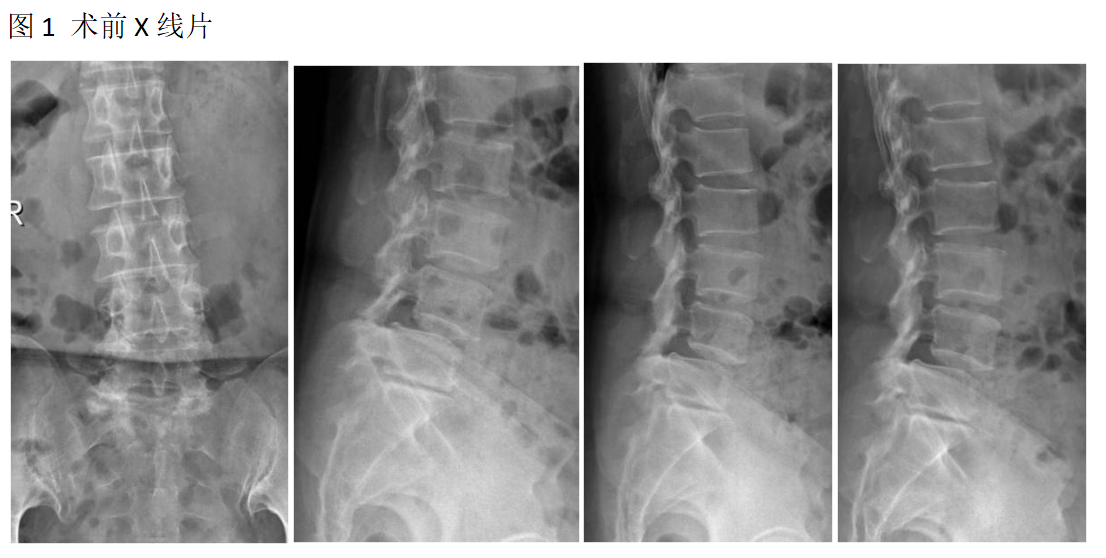

吕X,女,56岁。

主诉:腰疼及双下肢疼痛麻木伴活动受限3年加重半年。

查体:L4-5棘间及椎旁压痛,右下肢直腿抬高试验60°阳性,左下肢50°阳性,双下肢肌力肌张力正常。